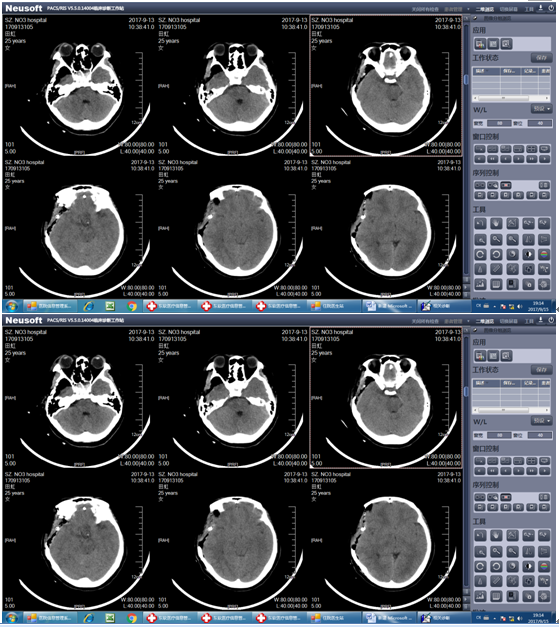

患者田某,患者于2017年9月12日23时左右过马路时不幸发生车祸,被摩托车撞伤后倒地,当即头痛,伴头晕、呕吐胃内容物多次,非喷射性。急送至我院急诊外科,查颅脑CT示:右颞顶部硬膜外血肿。入院当时患者神清,8分钟后患者病情迅速加重,陷入昏迷,呼之不应,查体先是右侧瞳孔变大,11分钟后患者双侧瞳孔直径散大直径6mm,对光反射消失,立即积极术前准备,同时急复查颅脑CT示:右颞顶部硬膜外血肿大量增加,量约90ml并脑疝形成,遂迅速启动绿色通道将患者由急诊外科直接送入手术室急诊行开颅手术治疗。

此时田某神志昏迷,口吐白沫,病情恶化迅速,情况危急,双侧瞳孔直径散大,脑疝形成,死亡率极高。我院神经外科唐忠主任与陈思、廖广生医师迅速为田某急诊行开颅右侧硬膜外血肿清除术+去骨瓣减压术。术程顺利,患者右侧额颞顶巨大硬膜外血肿完全清除,术中见静脉窦破裂,予以彻底止血,手术顺利。术后考虑病情危重由手术室送入综合ICU监护治疗。予呼吸机辅助通气,保持右侧头部硬膜外血肿引流管通畅、止血、预防感染、预防应激性溃疡、维持水电解质平衡、防止并发症、防止深静脉血栓形成等治疗。经过治疗后田某病情好转,术后第二天患者神志清楚,生命体征平稳,转回我科科继续治疗,现患者病情正在逐步恢复好转。

患者脑疝形成,死亡率极高。术前双侧瞳孔散大,脑疝形成,这种病人死亡率极高,患者很少存活,而田某生命得以延续,术后神志迅速恢复,得益于我院神经外科、急诊科、手术室、综合ICU、放射科等团队迅速而紧密地合作,对急重症颅脑患者开放绿色通道,手术快速精准,及时清除血肿减压,使得患者在最短时间获得迅速救治。我科将继续努力,为颅脑患者带来福音。